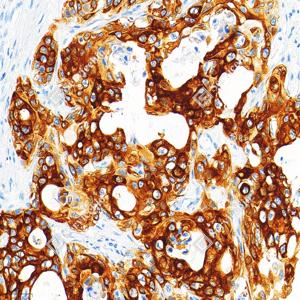

IHC检测Cytokeratin 17蛋白(货号 GB122104). 样品: 人肝内胆管腺鳞癌, 4%多聚甲醛 (货号G1101) 固定12-24小时. 抗原修复: 柠檬酸抗原修复液(干粉, pH 6.0) (G1201), 高压锅均匀喷气计时2分钟. —抗: 1: 1000稀释, 4℃ 孵育过夜. 二抗: S-vision免疫组化多聚二抗(山羊抗小鼠), 即用型(货号G1301), 室温孵育20分钟. |